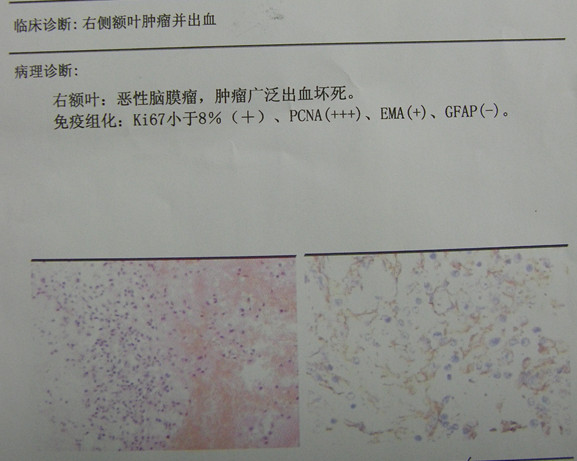

病理报告:恶性脑膜瘤

术后3周CT复查:水肿消退,肿瘤清除彻底。患者已下床活动并出院康复,嘱其定期复查酌情放疗。